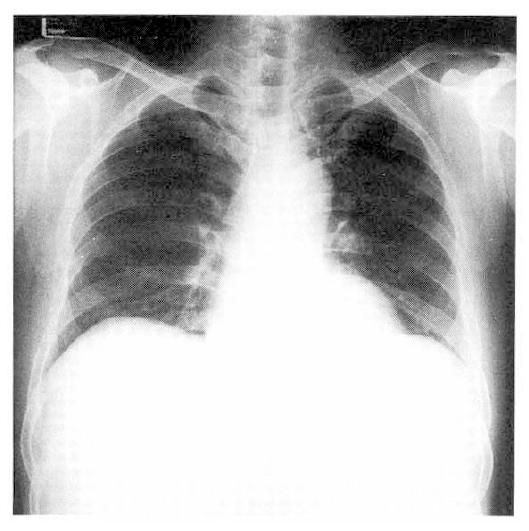

On second admission day, a standard fiberscopic endoscope was inserted. Six ml of five percent EO was injected around the base of visible varices in the esophagus for bleeding control. Immediately after injection, he was comfortable. Thirty-six hours later, dyspnea developed suddenly. He denied sputum, hemoptysis and cough. On physical examination, he was alert, but acutely distressed. Vital signs were blood pressure 120/80 mmHg, pulse rate 118/min, and temperature 37.1°C. Respiratory rate was 34/min and labored. The jugular vein was not engorged. On auscultation, crackles were heard on entire lung fields. The heart sound was rapid, but regular without gallop sound. The chest PA showed diffuse infiltration of alveolar densities on entire lung fields(Fig. 2). At room air, arterial blood gas analysis revealed pH; 7.46, pCO2; 34.7 mmHg, pO2; 53.8mmHg, HCO3; 24.7mmol/L, and O2SAT; 88.2%. The patient received supportive treatments including oxygen inhalation with partial rebreathing mask without application of mechanical ventilation and PEEP. Two days later, dyspnea subsided gradually and the chest PA revealed normal findings completely.

Fig. 2.

Thirty-six hours after the injection of the ethanolamine oleate, chest PA shows diffuse alveolar infiltrates on both lung fields.